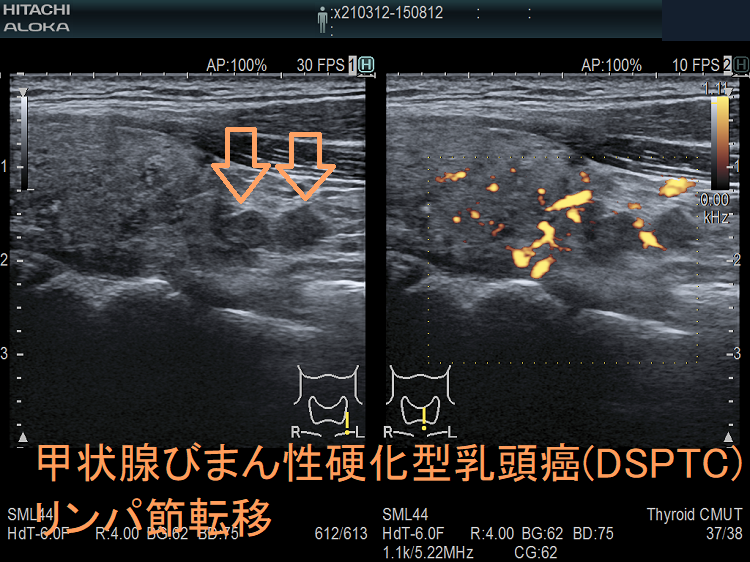

- 進行が早く、甲状腺内浸潤、両外側リンパ節転移の出現まで短期間

早期に頸部リンパ節転移(95.9%)(※診断時、ほぼ全例で頸部外側リンパ節転移)や肺転移(約5%)

対側中央区域リンパ節転移(50%)、対側リンパ節転移(66.7%)

- 甲状腺超音波(エコー)検査において、不均一な病変で

等エコー(48.4%)、びまん性粒状石灰化(52.3%)、血流は乏しい(71.6%)

- 甲状腺エコーで、境界不明瞭で不均質な病変;等エコー(48.4%)、びまん性粒状石灰化(52.3%)、血流は乏しい(71.6%)[Clin Radiol. 2022 May;77(5):e356-e362.]

(エコー画像;Ultrasonography. 2017 Apr 36(2) 103–110.)